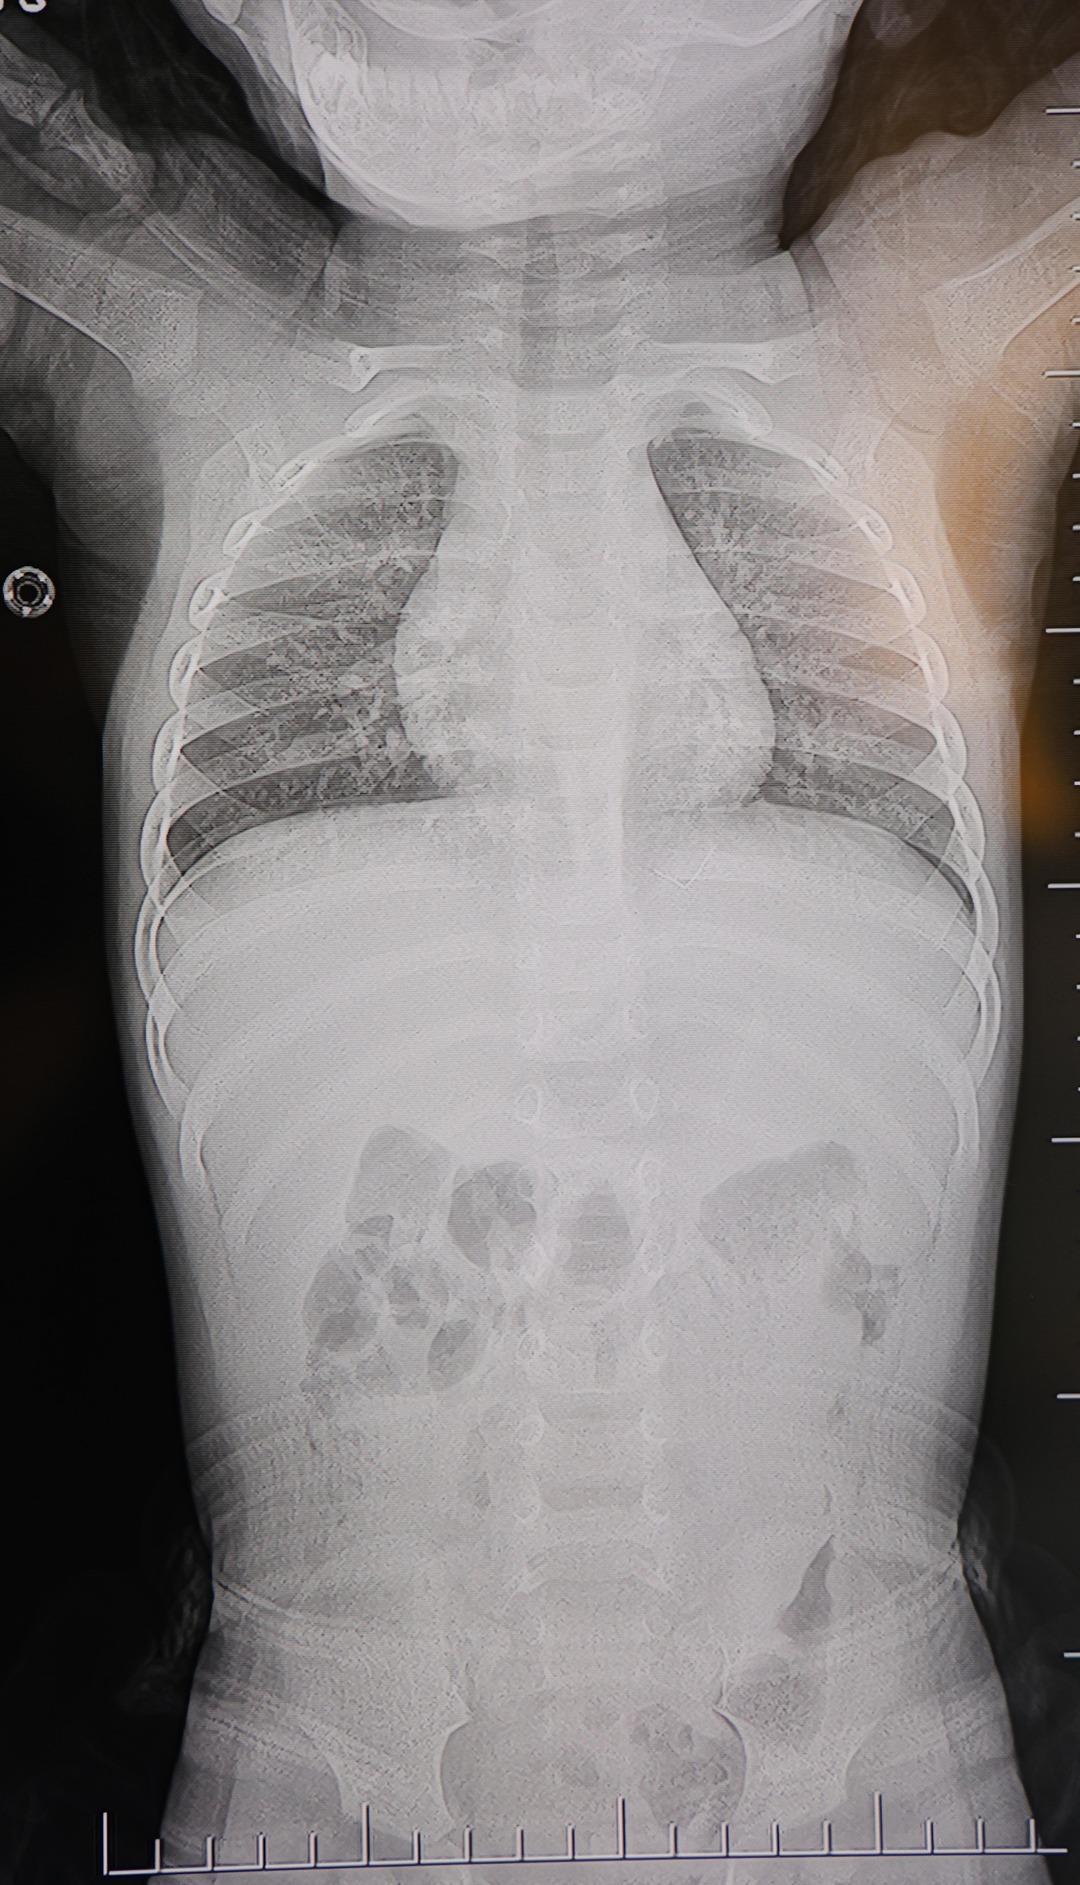

Yapılan tetkiklerde, yabancı cismin cilt altında, omurilik kanalına yakın bir bölgede olduğu ve akciğer zarına doğru ilerlediği belirlendi.

Çıkarılan cismin, ince zımba teline benzer metal bir tel olduğu ve yaklaşık 2 santimetre uzunluğunda bulunduğu tespit edildi. Hasta, aynı gün taburcu edildi.

Konuya ilişkin açıklama yapan Prof. Dr. İdris Altun, "Sırtında yabancı bir cisim olduğu söylenmiş ancak çıkarılamayacağı ve 8 yaşına kadar beklenmesi gerektiği ifade edilmişti. Bize başvurduğunda yaptığımız tetkiklerde, cilt altında, omurilik kanalına çok yakın ve akciğer zarına doğru ilerleyen bir yabancı cisim tespit ettik. Hastamızı tamamen uyutmadan, lokal anestezi ve sedasyon eşliğinde müdahale ederek lezyonu tamamen çıkardık. Çıkardığımız cismin ince zımba teline benzer, yaklaşık 2 santimetre uzunluğunda metal bir tel olduğunu gördük. Bu yabancı cisim alınmasaydı, bölgede enfeksiyon gelişebilirdi. Enfeksiyon sonucu omurilik kanalında ciddi hasarlar oluşabilir, çocuk büyüdükçe cismin hareket etmesine bağlı olarak omurilikte zedelenmeler meydana gelebilirdi. Ayrıca yana doğru ilerleyerek akciğer zarına ve akciğere batma riski vardı. Bu da enfeksiyona ve ilerleyen süreçte tümörle karışabilecek tablolara neden olabilirdi. Şu an hastamız gayet sağlıklı. Gerekli kontrolleri yaptık ve aynı gün taburcu ettik" dedi.